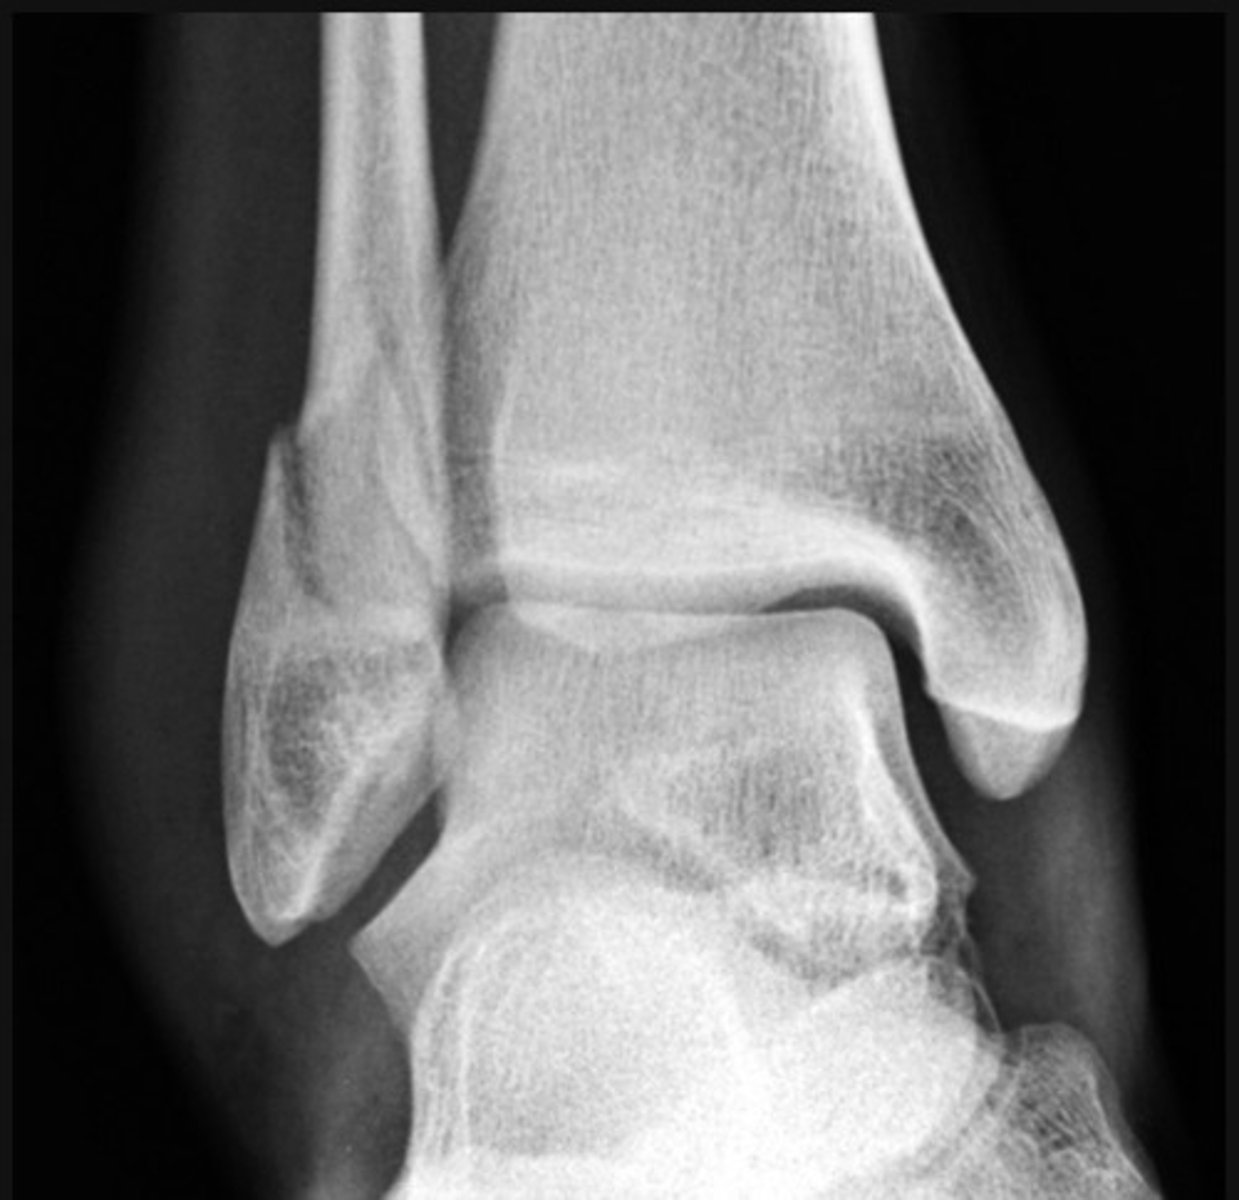

Weber C

There is a transverse medial malleolus fracture

The distal tibiofibular joint is also widened